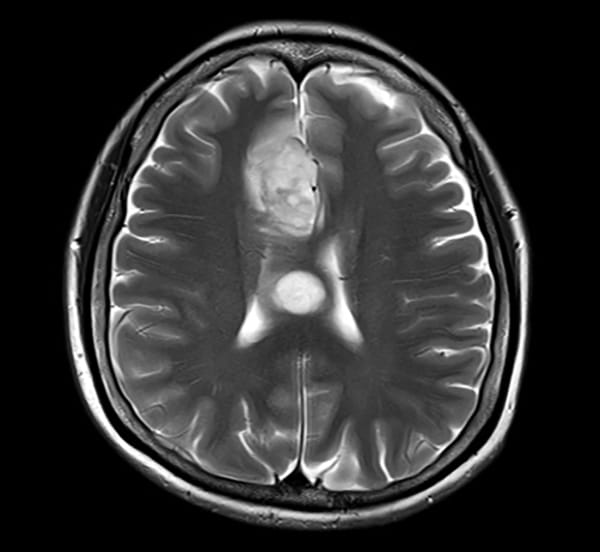

T1WI低信号、T2WI高信号、FLAIR高信号、DWIでやや高信号の腫瘤。Gdで腫瘤は造影されず、DSC-Perfusionでは辺縁~中心部に一部血流の高い部分あり。MRスペクトロスコピーではCho上昇とNAA低下がみられる。Low grade gliomaを疑う。後日、摘出手術が施行され、病理診断はoligodendroglioma NOS(Grade 2)であった。